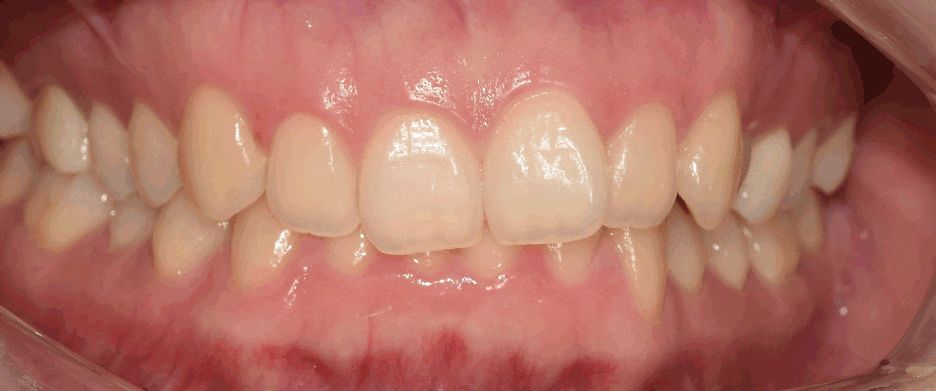

『최종 결과』

과개교합 교정 치료기간은 대략, 11개월 가량이

소요되었습니다. 생각보단 빨리 끝났죠?

이렇게, 치료가 끝맺음이 되면서

환자께서 하셨던 말씀이

“선생님, 저 치아가 더 만들어진 거 같아요 ㅋㅋㅋ

되게 음식이 잘 씹히네요?” 라는 말씀을 하셨죠..

자 이렇게, 사진의 변화를 보니

어떤식으로 구강 내 환경이 변화되는지를

한 눈에 보실 수 있을겁니다.

치료 기간 2020.04.08 ~ 2021.05.18